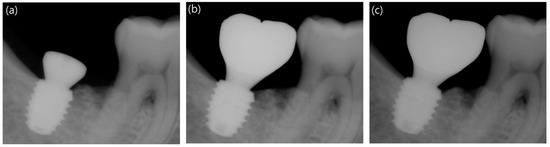

2.3.5. Measurement of Marginal Bone Loss

3.4. Comparison of Marginal Bone Loss between the Long and Short Implants

| 12-week follow up | Mesial | −0.22 ± 0.98 | -0.15 ± 0.79 | 0.893 |

| Distal | 0.08 ± 0.81 | 0.20 ± 0.78 | 0.728 | |

| Avg. | −0.07 ± 0.78 | 0.03 ± 0.63 | 0.885 | |

| 48-week follow up | Mesial | −0.15 ± 0.94 | -0.13 ± 0.82 | 0.719 |

| Distal | 0.27 ± 0.80 | 0.23 ± 0.92 | 0.573 | |

| Avg. | 0.06 ± 0.82 | 0.05 ± 0.77 | 0.655 | |